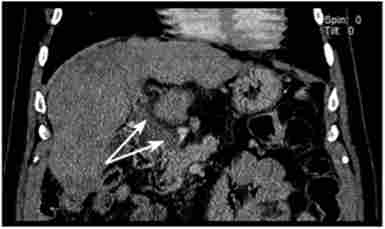

У деяких випадках має місце зметана форма блокади портального кровообігу, яка може бути обумовлена цирозом печінки і вторинним тромбозом вен портальної системи (рис. 17.3).

Змішана форма портальної гіпертензії. Комп'ютерно-томографична ангіограма (тромбоз ворітної вени на тлі цирозу печінки - вказано стрілкою)

Мал. 173. Змішана форма портальної гіпертензії. Комп'ютерно-томографична ангіограма (тромбоз ворітної вени на тлі цирозу печінки - вказано стрілкою)